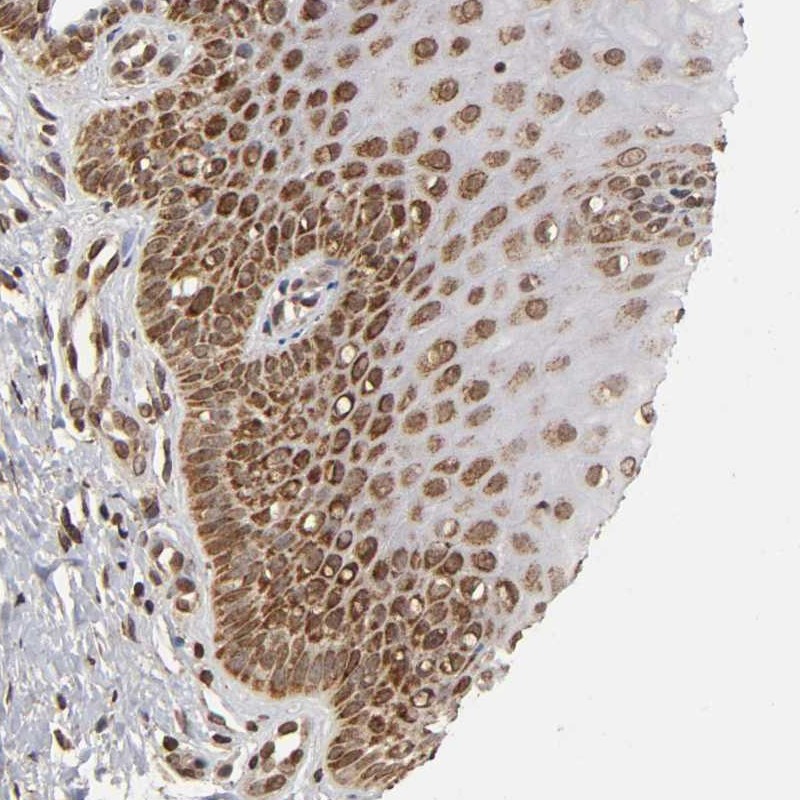

Immunohistochemical staining of human cervix, uterine shows cytoplasmic and nuclear positivity in squamous epithelial cells.